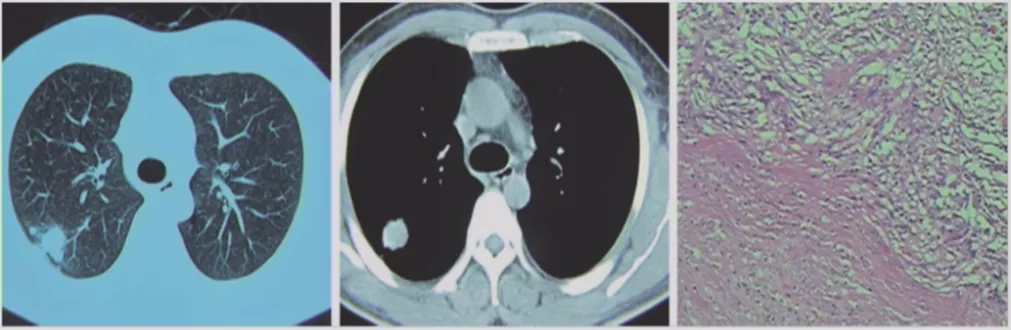

肺隐球菌病

肺隐球菌病往往在手术或者活检后才能明确诊断,肺泡腔部分被隐球菌和炎症细胞占据,病情逐渐发展病灶转为实性结节,无GGO成分。可以在相对健康的人群中发生,包括体质很好,没有基础疾病的人群。因为结节做手术,最后病理是隐球菌病的不在少数。因此肺隐球菌病有相当一部分是怀疑肺癌,在手术以后才明确诊断。所以在做鉴别诊断时,要注意还有隐球菌,而隐球菌抗原检查可以提供鉴别依据。